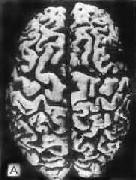

一、Alzheimer病Alzheimer病又称初老期痴呆,是以进行性痴呆为主要临床表现的大脑变性性疾病,起病多在50岁以后。随着人类寿命的延长,本病的发病率呈增高趋势。按照美国的诊断标准,上海60岁以上人群发病率为3.46%。65岁以上人群为4.61%。临床表现为进行性精神状态衰变,包括记忆、智力、定向、判断能力、情感障碍和行为失常甚至发生意识模糊等。患者通常在发病后5~6年内死于继发感染和全身衰竭。 【病理变化】 肉眼观,脑萎缩明显,脑回窄、脑沟宽,病变以额叶、顶叶及颞叶最显着(图16-32),脑切面可见代偿性脑室扩张。

图16-32 初老期痴呆的脑 示脑明显萎缩(A),与正常脑(B)的对比 镜下,本病最主要的组织病变有:老年斑,神经原纤维缠结,颗粒空泡变性,Hirano小体等。 (1)老年斑:为细胞外结构,直径为20~150μm,最多见于内嗅区皮质、海马CA-1区,其次为额叶和顶叶皮质。银染色显示,斑块中心为一均匀的嗜银团,刚果红染色呈阳性反应,提示其中含淀粉样蛋白,其中含该蛋白的前体β/A-4蛋白及免疫球蛋白成分。中心周围有空晕环绕,外围有不规则嗜银颗粒或丝状物质。电镜下可见该斑块主要由多个异常扩张变性之轴索突触终末构成(图16-33)。